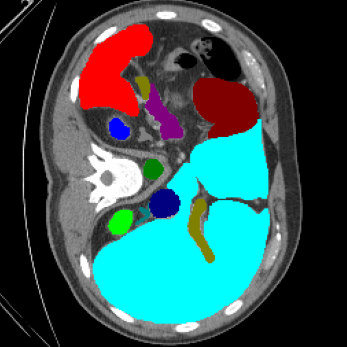

| Ground Truth | LoGoNet | DiNTS Search |

|---|---|---|

![]() |

We begin by qualitatively inspecting our model. Figure 3 compares the output of LoGoNet to the best performing baseline model in BTCV dataset, i.e., DiNTS Search (more qualitative comparisons can be found in appendix section 11). We see that our model particularly excels in segmenting organ boundaries. This can be attributed to our effective strategy for extracting local-range dependencies, which plays a crucial role in extracting details from input data. Our model’s adeptness in capturing long-range dependencies allows it to grasp contextual information that extends over significant distances within the data. Simultaneously, its proficiency in handling short-range dependencies ensures precision in capturing localized patterns.